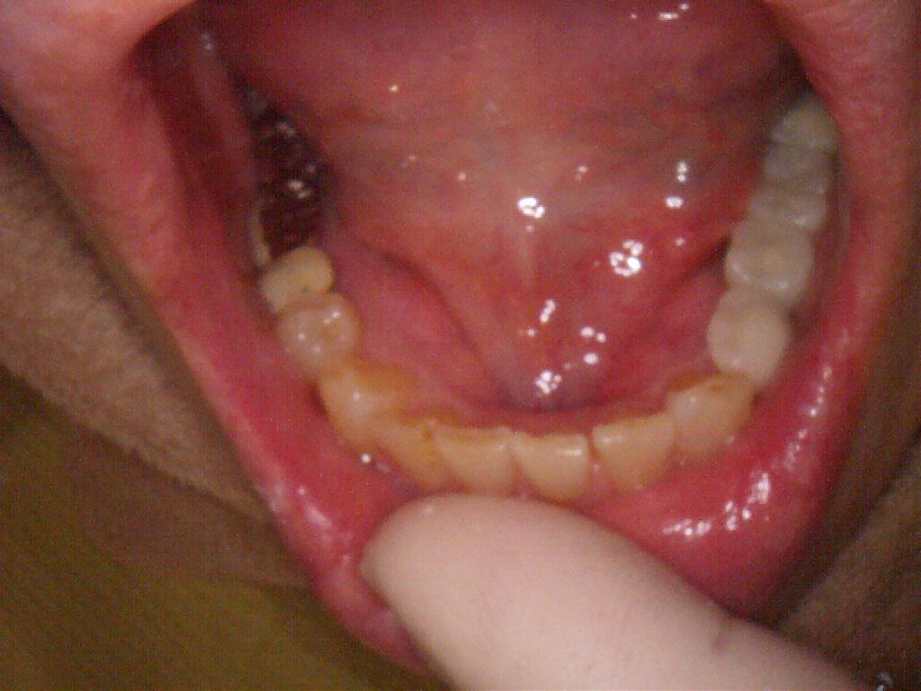

60代男性|奥歯で噛みづらい

-

治療前

- 治療名称

- 右下56番パーシャルデンチャー部のインプラント治療

- 患者の症状

- 右下56番にパーシャルデンチャーを装着しており機能及び審美的に問題を抱えている。

- 治療内容

- まず、CT撮影による精密な骨の分析・治療計画を立てガイドを使いインプラント埋入しインプラントが骨と結合するのを待つ間に仮の歯を入れます。その後本歯を作成して装着しました。

- 治療期間・回数

- インプラント埋入からジルコニアセットまで三か月半

- 費用

※自由診療となります - ■総額:¥660,000(税込み) ■内訳:埋入(ガイド込み)¥200,000×2、仮歯¥20,000×2、被せ物¥80,000×2